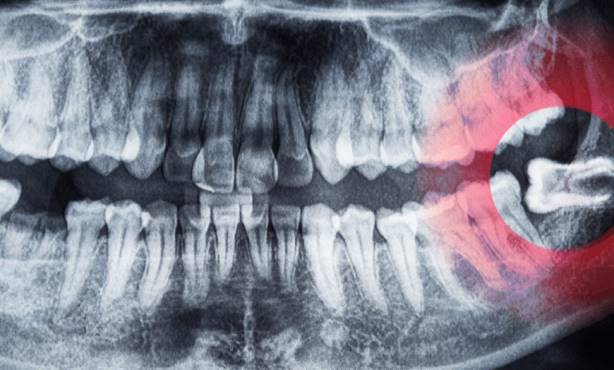

Per diagnosticare un problema al dente del giudizio con un nervo infiammato, il dentista eseguirà innanzitutto un esame fisico dell’area interessata. Potrà anche effettuare delle radiografie per determinare la posizione dei denti del giudizio e l’entità di eventuali danni o infezioni. In alcuni casi, può essere necessaria una TAC per avere una visione più dettagliata del problema.